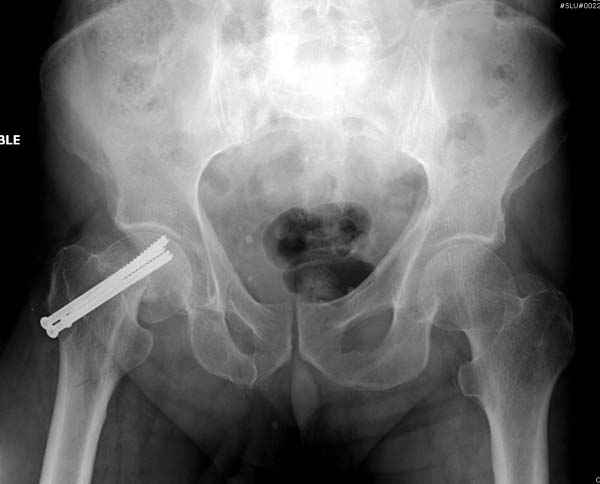

На второй день после выписки упал дома. Снимки приложены. Коллеги рекомендуют удаление шурупа и вытяжение. Что делать?

Правильно, ситуация изменилась, как говорят у нас теперь "different animal", надо решать проблему подвертельного перелома. При наличии различных вариантов фиксаторов, включая Страйкер Гамма 3, мы выбрали DePuy Antegrade Trachanteric Nail из-за многовариантности проксимальной фиксации и двойного изгиба. Вводится через вертел под 8 градусным углом, и есть достаточный передний диафизарный изгиб, предупреждающий пенетрацию дистального переднего кортекса.

Но ведь и головка бедра сползла в варус - отчего ограничились только фиксацией подвертельного перелома, а не убрали винты и не сделали репозицию шейки?